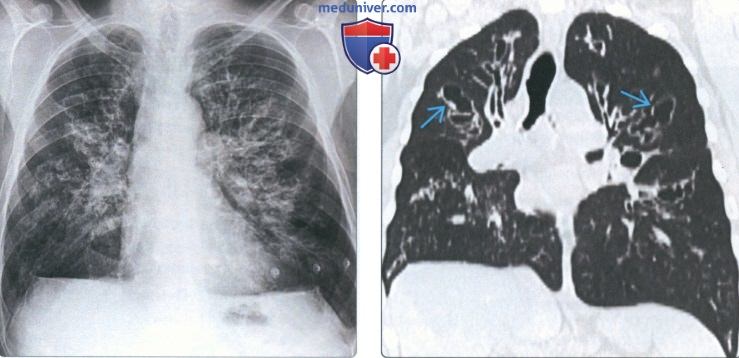

Фотографии, демонстрирующие обнаруженное усиление легочного рисунка

Раздел: Фотодневник открытий